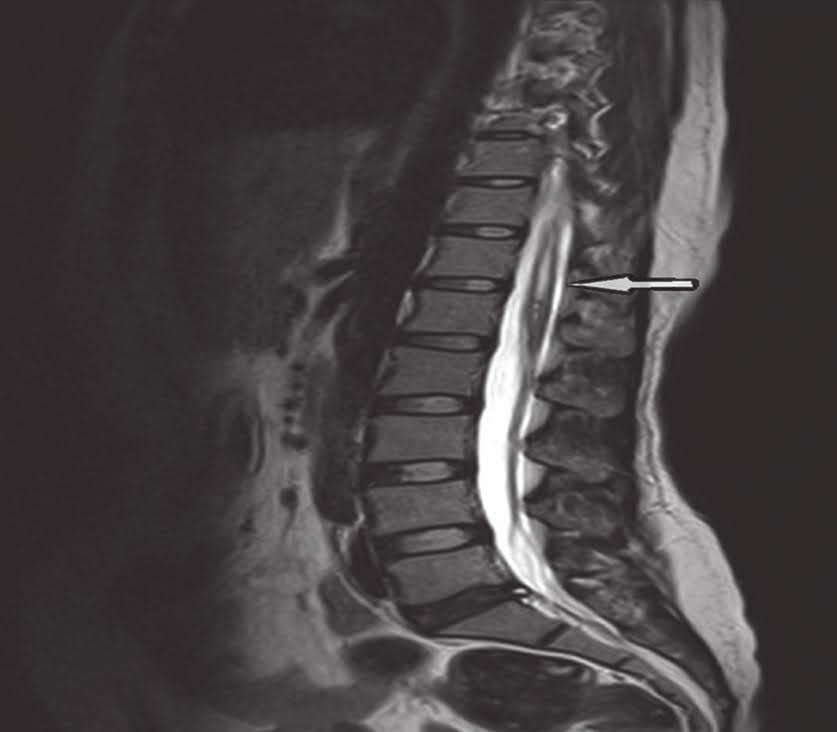

Name of condition seen in these images

https://photos.app.goo.gl/6sqJTrBaow6akuWD9

What is an anterolisthesis?